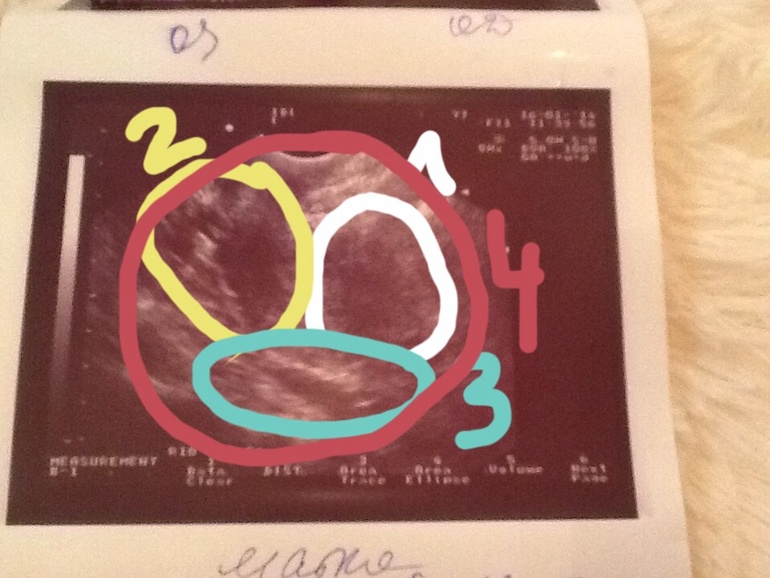

Ждем дня Х (Признаки беременности / Тесты)Не могу понять,где на снимке матка))))))может кто понимает????можно обвести в фоторедакторе,просвятить дурочку!!

Нету крестиков,Кристин,просто фото и все,я вижу просто три темных пятна,а что из них матка...???

два разных УЗИ, это матка, обычно там крестики и черточки, о которых я говорила)

Мне просто показалось странная форма. В отклонение кзади ничего страшного. Она в разные дни цикла, кстати, может принимать разное положение))))